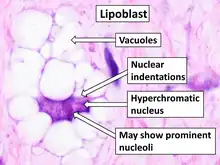

| Histopathology of liposarcoma, H&E stain:[1] - | |

Histopathologic analyses of MLS (see Figs. 3 and 4 in the below Histopathology of liposarcomas section) reveals cells scattered throughout a myxoid matrix (i.e. a connective tissue background that appears more blue or purple than the red color of normal connective tissue when these tissues are properly prepared, H&E stained, and viewed microscopically). These cells are lipoblasts, some of which are signet ring-shaped (a shape suggesting that the cell may be neoplastic), oval-shaped, or round-shaped.[40] MLS tumors may be hypercellular and contain solid sheets of round cells that comprise at least 5% of all cells or low cellularity populated with cells that have bland nuclei and <5% round cells in a background of curving capillaries resembling a chicken-wire pattern. Tumors that contain at least 5% round cells are classified as high-grade while those with <5% round cells are classified as low-grade.[39] High-grade MLS tumors typically take a more aggressive clinical course than low-grade MLS tumors.[40]

On histopathologic analyses, MPL tumors consist of areas resembling conventional myxoid liposarcoma; these areas, which represent 30–50% of the total tumor areas, have an abundant myxoid matrix, a well-developed capillary vasculature, bland cells that are round and/or slightly spindle-shaped, vacuolated lipoblasts, and multinucleated cells shaped like small flowers. However, these areas also contain a scattering of highly pleomorphic cells that show greater degrees of nuclear enlargement and irregularity than the cells seen myxoid liposarcoma tumors. Other areas of MPL tumors are more cellular and consist of rapidly growing and highly pleomorphic lipoblasts.[62]